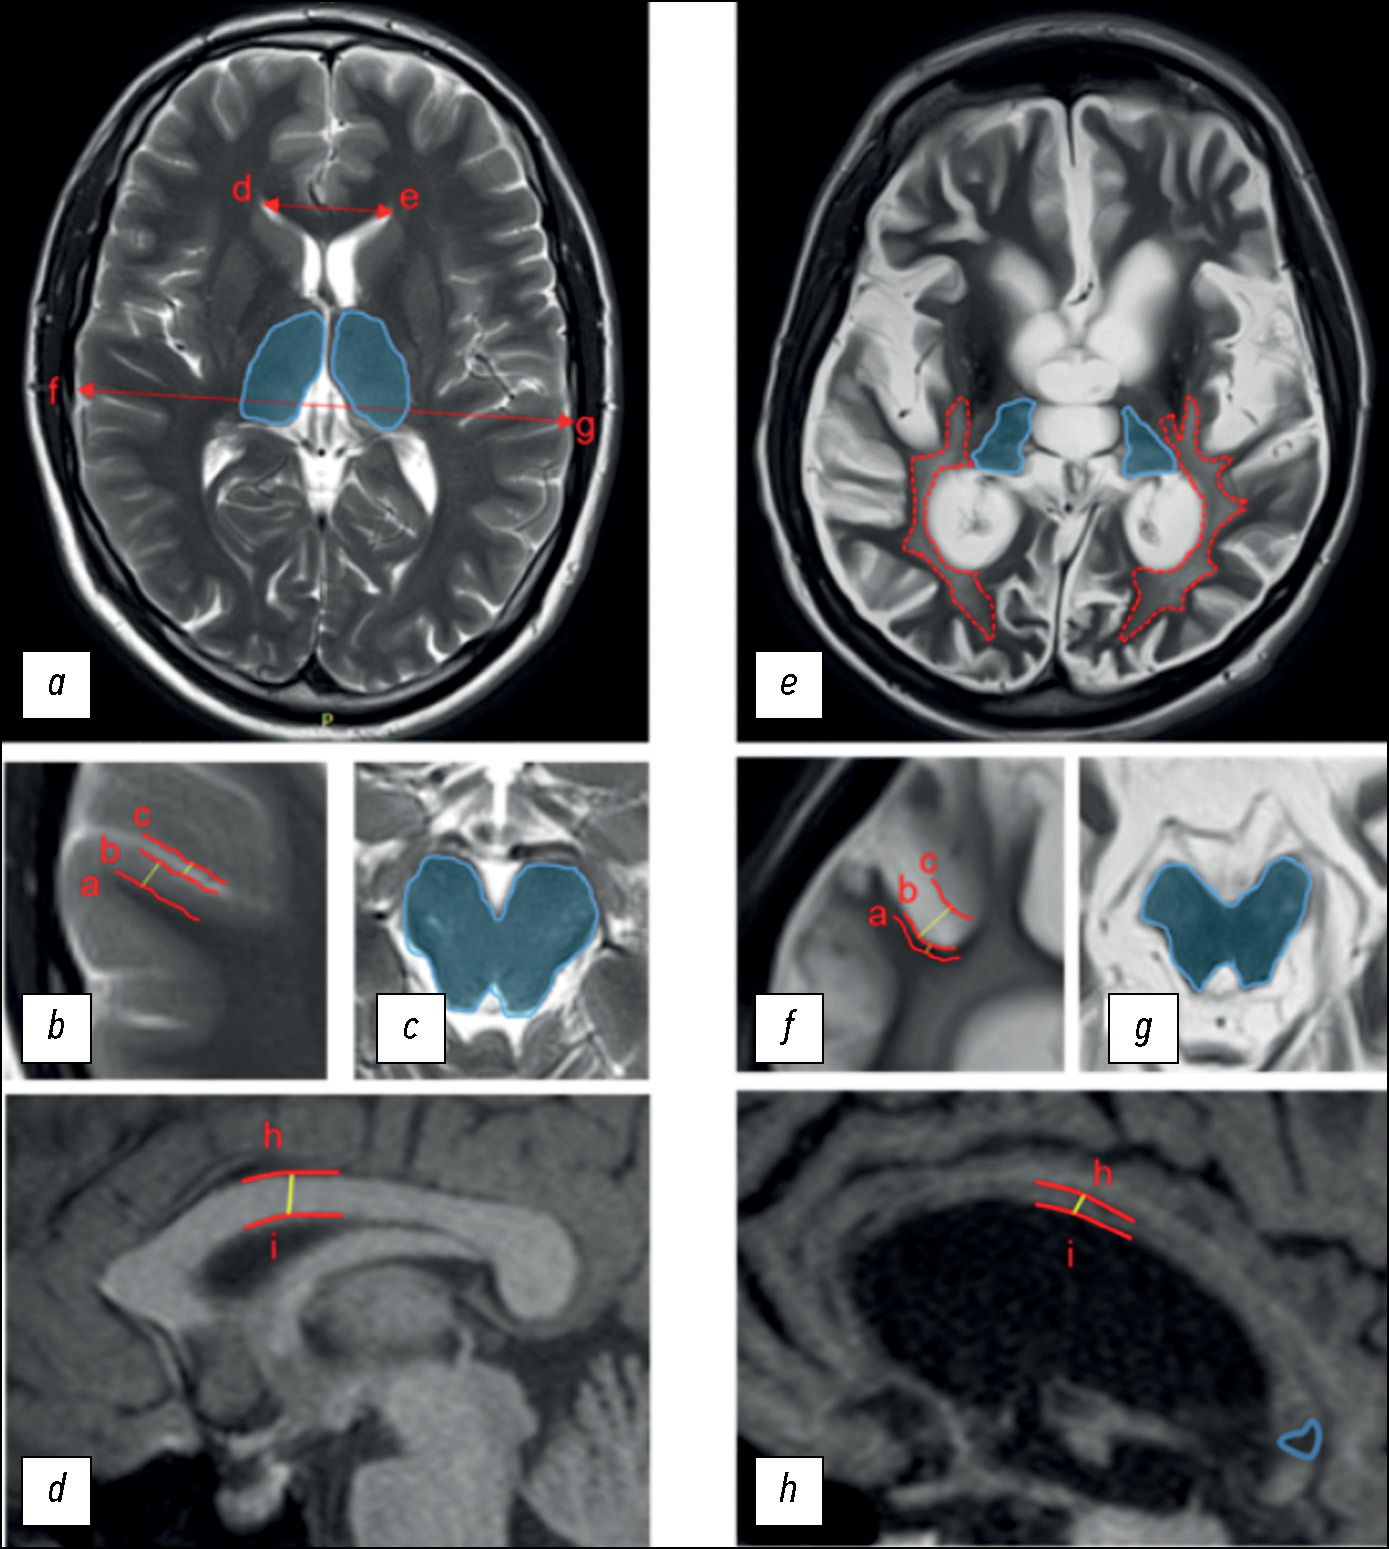

Comparison of non-contrast magnetic resonance perfusion and phase-contrast angiography for the quantitative assessment of cerebral blood flow: a prospective cross-sectional study

Abstract

BACKGROUND: The validation of quantitative cerebral blood flow assessment using non-contrast magnetic resonance imaging remains unresolved. The optimal approach involves applying a method based on a different physiological model to enhance the reliability of the obtained data.

AIM: To verify the results of quantitative cerebral tissue blood flow assessment using non-contrast MRI against quantitative 2D phase-contrast angiography in healthy adults.

METHODS: The prospective study enrolled healthy adults (aged 18–75 years). Cerebral perfusion was assessed using non-contrast magnetic resonance imaging, while macrovascular blood flow was measured in the vertebral and internal carotid arteries using quantitative 2D phase-contrast angiography. Brain volume and relative mass were evaluated based on T1-weighted image segmentation. Macrovascular blood flow values were converted into tissue perfusion metrics through mathematical adjustment accounting for brain mass.

RESULTS: In the study 80 adults were examined using both methods. Non-contrast magnetic resonance imaging revealed mean perfusion values of 17.88 ± 2.39 mL/100g/min in white matter and 42.06 ± 7.13 mL/100g/min in gray matter, with total cerebral perfusion at 59.63 ± 8.56 mL/100g/min. Total cerebral perfusion calculated from phase-contrast angiography and arterial blood flow velocity was 58.96 ± 8.16 mL/s. A strong positive correlation was found between total cerebral perfusion values derived from non-contrast magnetic-resonance and phase-contrast angiography (r = 0.892; p < 0.001).

CONCLUSION: A strong positive correlation was demonstrated between cerebral perfusion values obtained via non-contrast magnetic resonance imaging and phase-contrast angiography, despite their reliance on distinct physiological models.